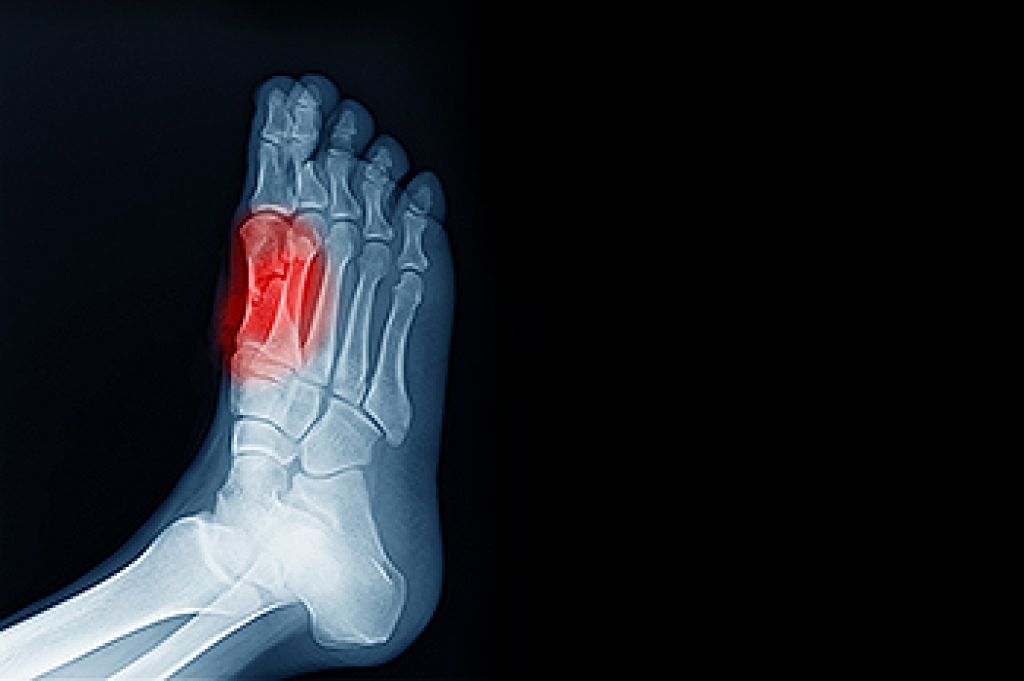

Sesamoiditis

Sesamoiditis is a condition of the foot that affects the ball of the foot. It is more common in younger people than it is in older people. It can also occur with people who have begun a new exercise program, since their bodies are adjusting to the new physical regimen. Pain may also be caused by the inflammation of tendons surrounding the bones. It is important to seek treatment in its early stages because if you ignore the pain, this condition can lead to more serious problems such as severe irritation and bone fractures.